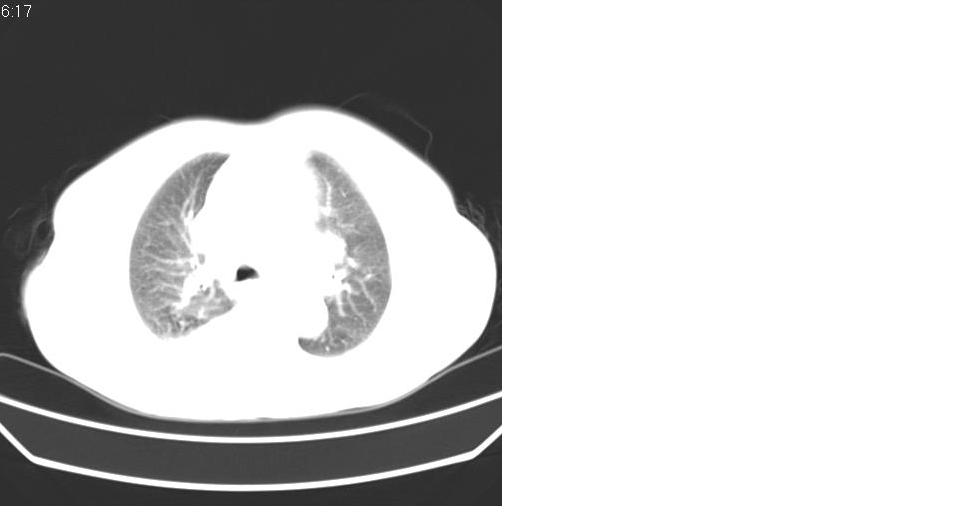

以下是引用liaizhi在2007-7-11 15:41:00的发言:[br]两肺纹理增粗,肺门影增大,气管支气管通畅。升主动脉壁及冠状动脉壁钙化。左房左室稍扩大。心包积液,胸腔积液。考虑冠心病并心功能不全,肺水肿,胸腔积液。

以下是引用zhangzhongshou在2007-7-11 13:16:00的发言:[br]1、冠状动脉钙化[br]2、心包积液[br]3、右侧胸腔积液[br]大家都考虑心衰,冠状动脉钙化、肺纹理增强,胸腔积液、心包积液,表面上是支持,但是为什么右侧有较多积液,左侧没有呢? 如果用结核性胸膜炎,并结核性心包炎也可解释,请楼主进一步提供临床资料。

以下是引用zrs在2007-7-11 14:40:00的发言:[br]支持心衰,心衰所至的胸腔积液常常是右侧多